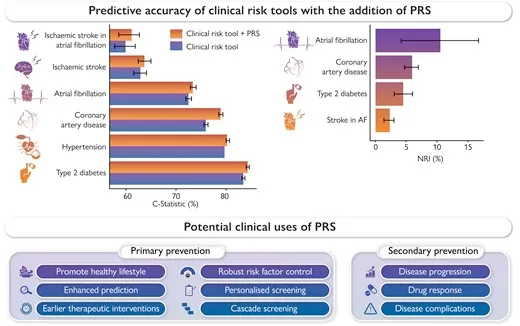

Harnessing polygenic risk scores for cardiovascular disease prevention: A guide for physicians

Atherosclerotic Cardiovascular disease (ASCVD) remains the leading cause of morbidity and mortality worldwide.

Implementing polygenic risk scores in the clinic: Use cases for cardiovascular disease risk management

The evidence is undeniable — polygenic risk score (PRS) testing enables healthcare providers to identify more high risk patients at an earlier stage, leading to better risk management and improved outcomes...

Using polygenic risk scores to enhance cardiovascular disease risk prediction

Cardiovascular diseases — a general term for a suite of diseases that affect the heart or blood vessels — account for one in three deaths globally and are a major drain on public health spending. Our risk of cardiovascular disease increases as we age...